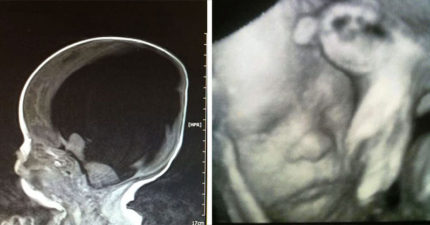

媽媽堅持生下「沒大腦寶寶」 4年後「大腦掃描照」震驚醫學界